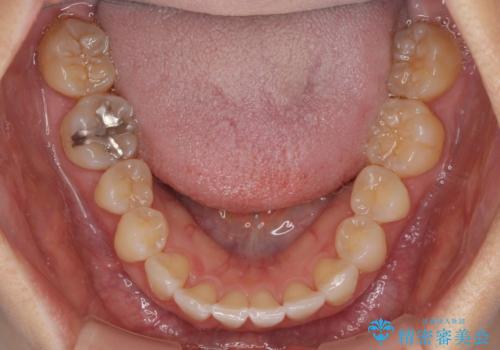

前歯のクロスバイト インビザライン矯正で改善

- むし歯治療を契機に、長年気にしていた前歯のクロスバイトの改善を希望された患者様です。

汚れが溜まりやすく、歯ぎしりがうまくできないため、インビザラインを用いて矯正治療を行うこととしました。

インビザラインによる前歯のクロスバイトの改善は、治療期間中に前歯でしか咬めない時期が続いたり、歯肉退縮や歯髄壊死のリスクが高まったりと、治療中にトラブルを抱えることがあります。

特に上顎側切歯(真ん中から2番目の歯)が舌側に引っ込んでいるケースは、インビザラインでは改善しきれないことがあると言われています。